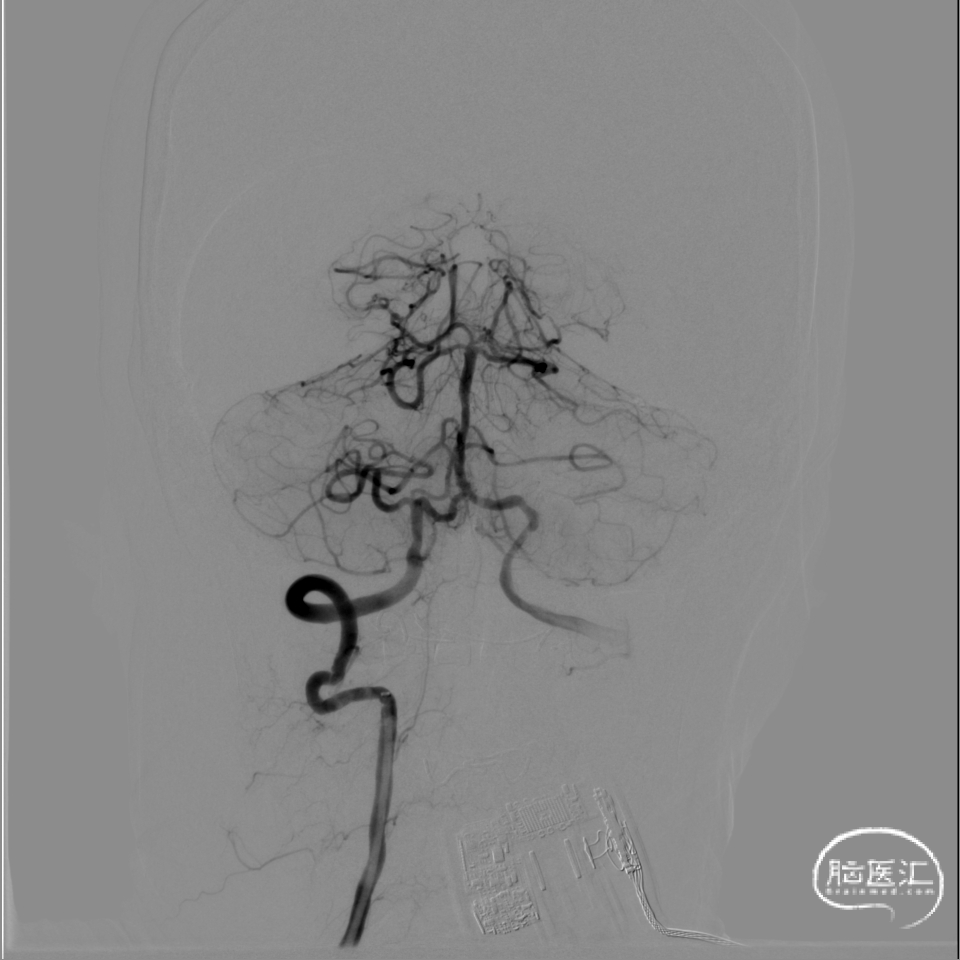

术前DSA影像:

3、椎基底动脉系统:

右侧椎动脉优势型。

左侧椎动脉血管纤细,远端可见基底动脉浅淡显影。

右侧椎动脉优势型,远端汇入基底动脉。

基底动脉中段重度狭窄,狭窄率约80%,双侧大脑后动脉可见显影。